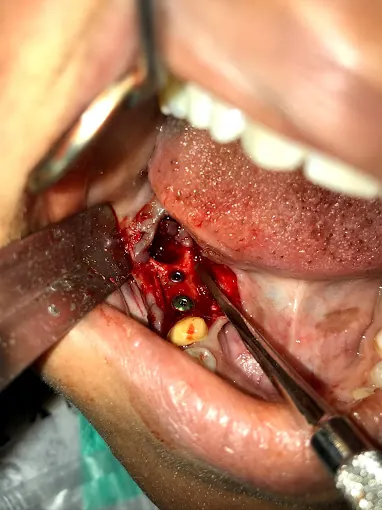

General Dentistry

Modern tools for precision

Our clinic uses advanced tools for accurate care.